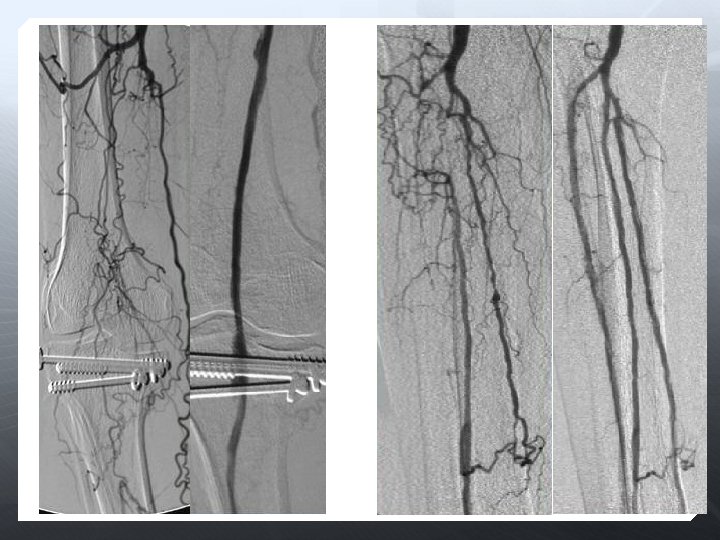

DİZALTI

Amaç uzun dönem açıklık değil, akımı restore etmek Olabildiğince çok damar restrore edilmeli Total ayak perfüzyonu iyileştirilir 3 damar run-off ile daha iyi SFA açıklığı sağlanır Oklüzyona karşı daha dirençli

Anjioplasti Subintimal anjioplasti Cutting-balon DEB Stent (BES, SES) DES Aterektomi Excimer laser